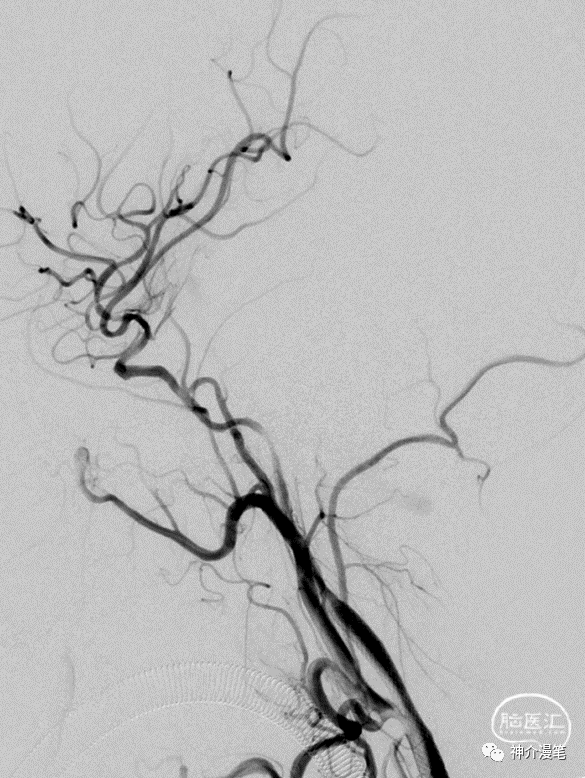

关键词:开环,镍钛,快交,无锥形支架。另外PRICISE支架8以下可以使用6F导引导管进行释放,这在部分通路迂曲的血管条件下尤为重要。支架释放过程不需要推挤支架,只需要把住推送杆后等张力扒开支架即可。

从上面这个简单的病例中可以看出,PRICISE支架对于血管局部走行的改变较小,基本顺延了原始的走行方向。这也是开环支架的一大优势。

Protege支架实际上在实际的使用过程中个人感觉和Pricise支架没有过多的区别。二者手感比较类似,区别点在于Protege有普通支架和锥形支架两种。

同样,从这个病例中我们仍然能看出支架放置后血管走行的趋势没有被过度的改变。但是下面这个病例,个人觉得支架种类的选择值得商榷。